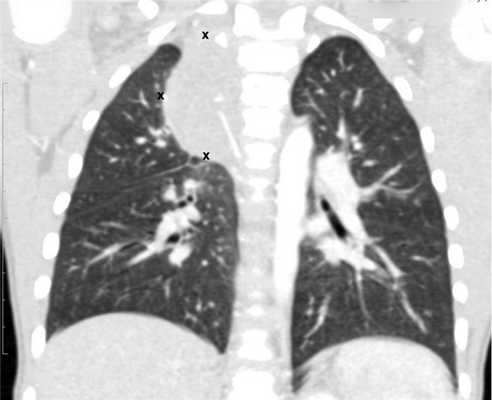

В отделении торакальной хирургии ДГКБ № 13 им. Н.Ф. Филатова Москвы с 2010 г. по декабрь 2014 г. находились под наблюдением 34 ребенка с диагнозом: объемное образование средостения. У 12 пациентов были выявлены солидные нейрогенные опухоли средостения (рис. 1). В аналогичный промежуток времени 16 детей с тем же диагнозом проходили лечение в ФНКЦ ДГОИ им. Дмитрия Рогачева, нейрогенные опухоли выявлены у 11 из них. За период с января 2012 г. по декабрь 2013 г. В двух клиниках всего 19 детям выполнены операции в объеме удаления опухоли с использованием торакоскопического доступа. 4 пациента в связи с большим объемом новообразования были оперированы из торакотомического доступа. Возраст детей от 1 мес до 7,5 года, средний возраст составил 1,5 года. Возраст 9 (47,3%) детей не превышал 12 мес. В наших наблюдениях среди пациентов с нейрогенными опухолями было 7 девочек и 12 мальчиков.

Рис. 1. Нейрогенная опухоль верхнего средостения.

Все дети проходили предоперационное обследование, включающее, помимо рутинных тестов, исследование онкологических маркеров, катехоламинов в моче, УЗИ, КТ и МРТ грудной клетки. При подозрении на злокачественный характер образования выполняли пункцию костного мозга и дополнительные исследования для выявления возможных метастазов в других органах.